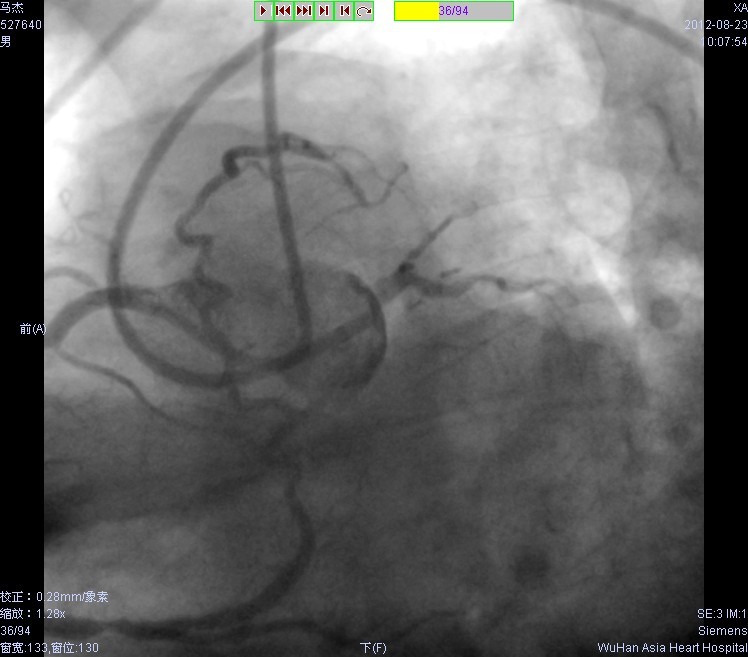

近日,我院苏晞、宋丹教授等独立成功实施了首例以逆向导引钢丝开通慢性完全闭塞(CTO)病变的经皮冠脉介入治疗术(PCI)(见图),术后患者康复效果良好。该手术为治疗我院冠心病患者开辟了新的途径,填补了我院独立在逆向导丝技术攻克CTO病变上的空白

逆向导丝打通前降支闭塞段后植入支架,前降支血流通畅

经右冠状动脉-前降支侧支逆向导丝打通前降支闭塞

前降支近段闭塞,双向造影显示右冠侧支供血